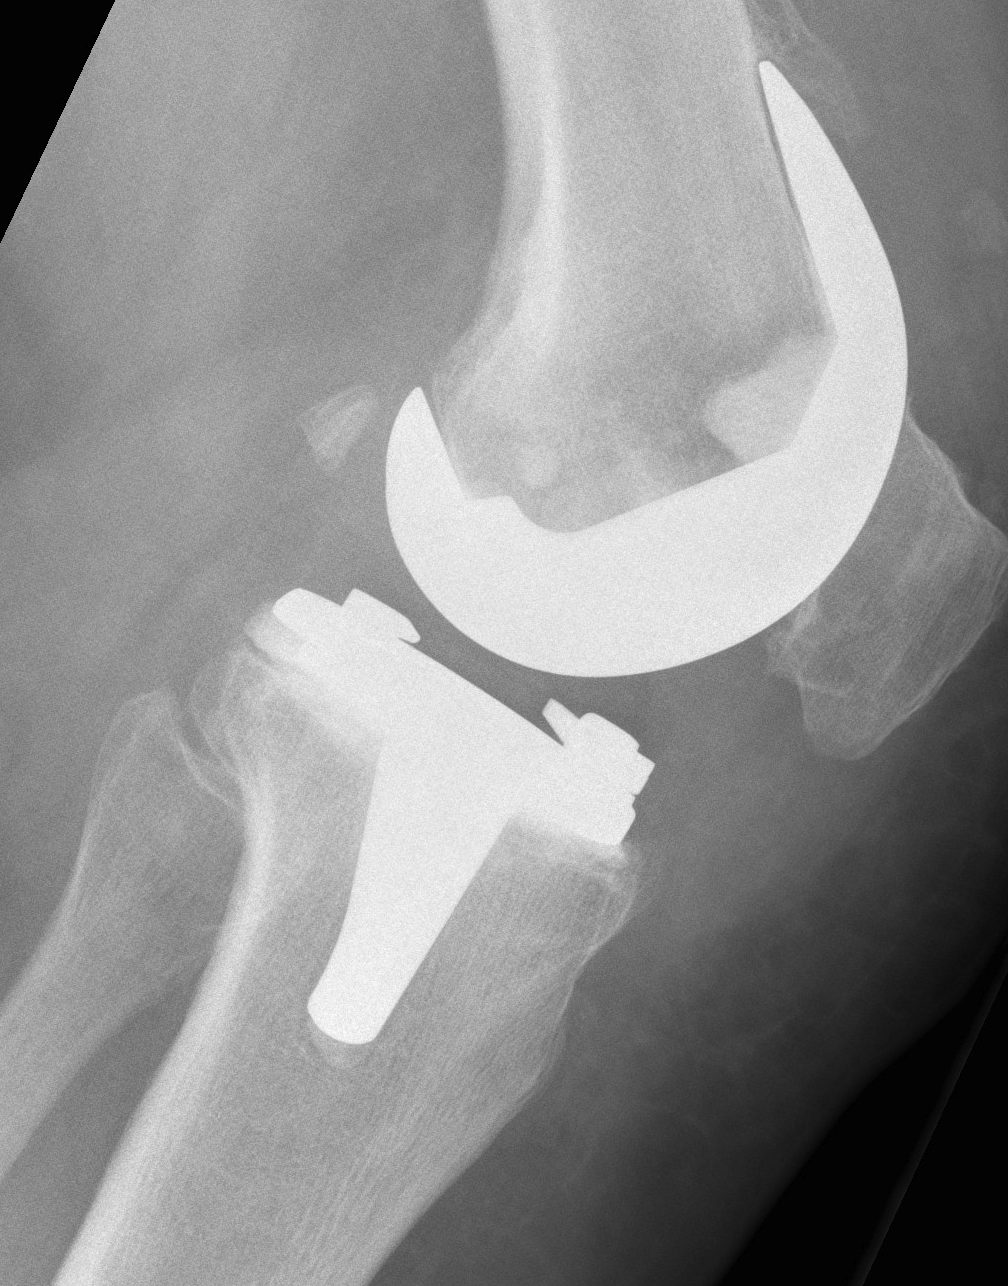

B. Standard +/- Revision TKR

2. Damaged Metaphysis

A One condyle

B Both

Management

A. Cement < 1cm

B. Augments < 2cm

C. Bone graft